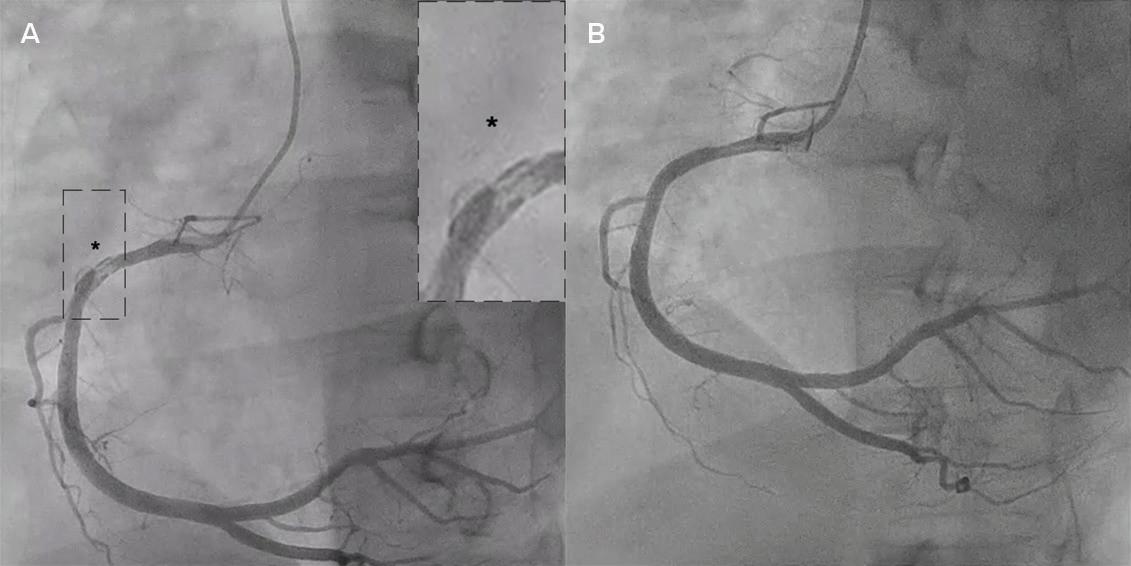

On the day of the procedure, the first balloon mitral valvotomy was performed from a right femoral approach using a 23–26 mm Accura balloon (Vascular Concepts) after transeptal access using an 8 Fr SL-1 sheath and a BRK-0 needle (St Jude Medical). A transeptal puncture was performed after proper needle tip position was confirmed by fluoroscopy (right anterior oblique, left anterior oblique and 90° lateral views) and transoesophageal echocardiography (bicaval and short axis views; Figure 3A). The mean left atrial pressure prior to the valvotomy was 31 mmHg. The balloon was inflated to 26 mm in the right anterior oblique 20° position under fluoroscopy (Figure 3B) because the patient was 160 cm tall. The mitral valve area increased to 2.2 cm2 without any additional mitral regurgitation, and the mean left atrial pressure decreased to 12 mmHg without any mitral valve gradient. Immediate transthoracic echocardiography showed that the mitral valve gradient had decreased to 7/2 mmHg with negligible mitral regurgitation.

electrophysiological study and for possible radiofrequency ablation (Figure 3C). The electrophysiologist proceeded with the ablation plan.

Figure 3: Transsepetal Puncture for Balloon Mitral Valvotomy and Electrophysiology Study in One Go A: Septal puncture using fluoroscopy and transesophageal echocardiography guidance. B: A 23–26 mm Accura balloon was inflated to 26 mm in the right anterior oblique view. Electrophysiological study using one quadripolar catheter for right ventricle pacing and one decapolar catheter in the coronary sinus.